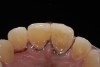

Fig 3. Preoperative view showing erosion of palatal surfaces of upper anteriors.

Figure 3

A 40-year-old female patient complained of short teeth and asked for various options to improve her smile. On clinical examination, the palatal surfaces of the maxillary anterior teeth were found to be eroded, with the residual tooth structure having a smooth and shiny appearance (Figure 1 through Figure 3). In MIP, no restorative space was available, as the lower anterior teeth fit tightly into the upper palatal surfaces, making this a clinically challenging situation to treat conservatively. In most cases of conventional treatment protocols, such upper teeth are devitalized and restored with crowns that structurally leave the teeth in a compromised condition.10